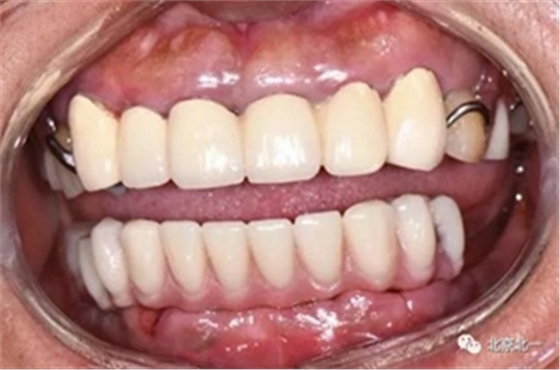

圖二十:永久修復(fù)咬合關(guān)系

圖二十五:口內(nèi)照。